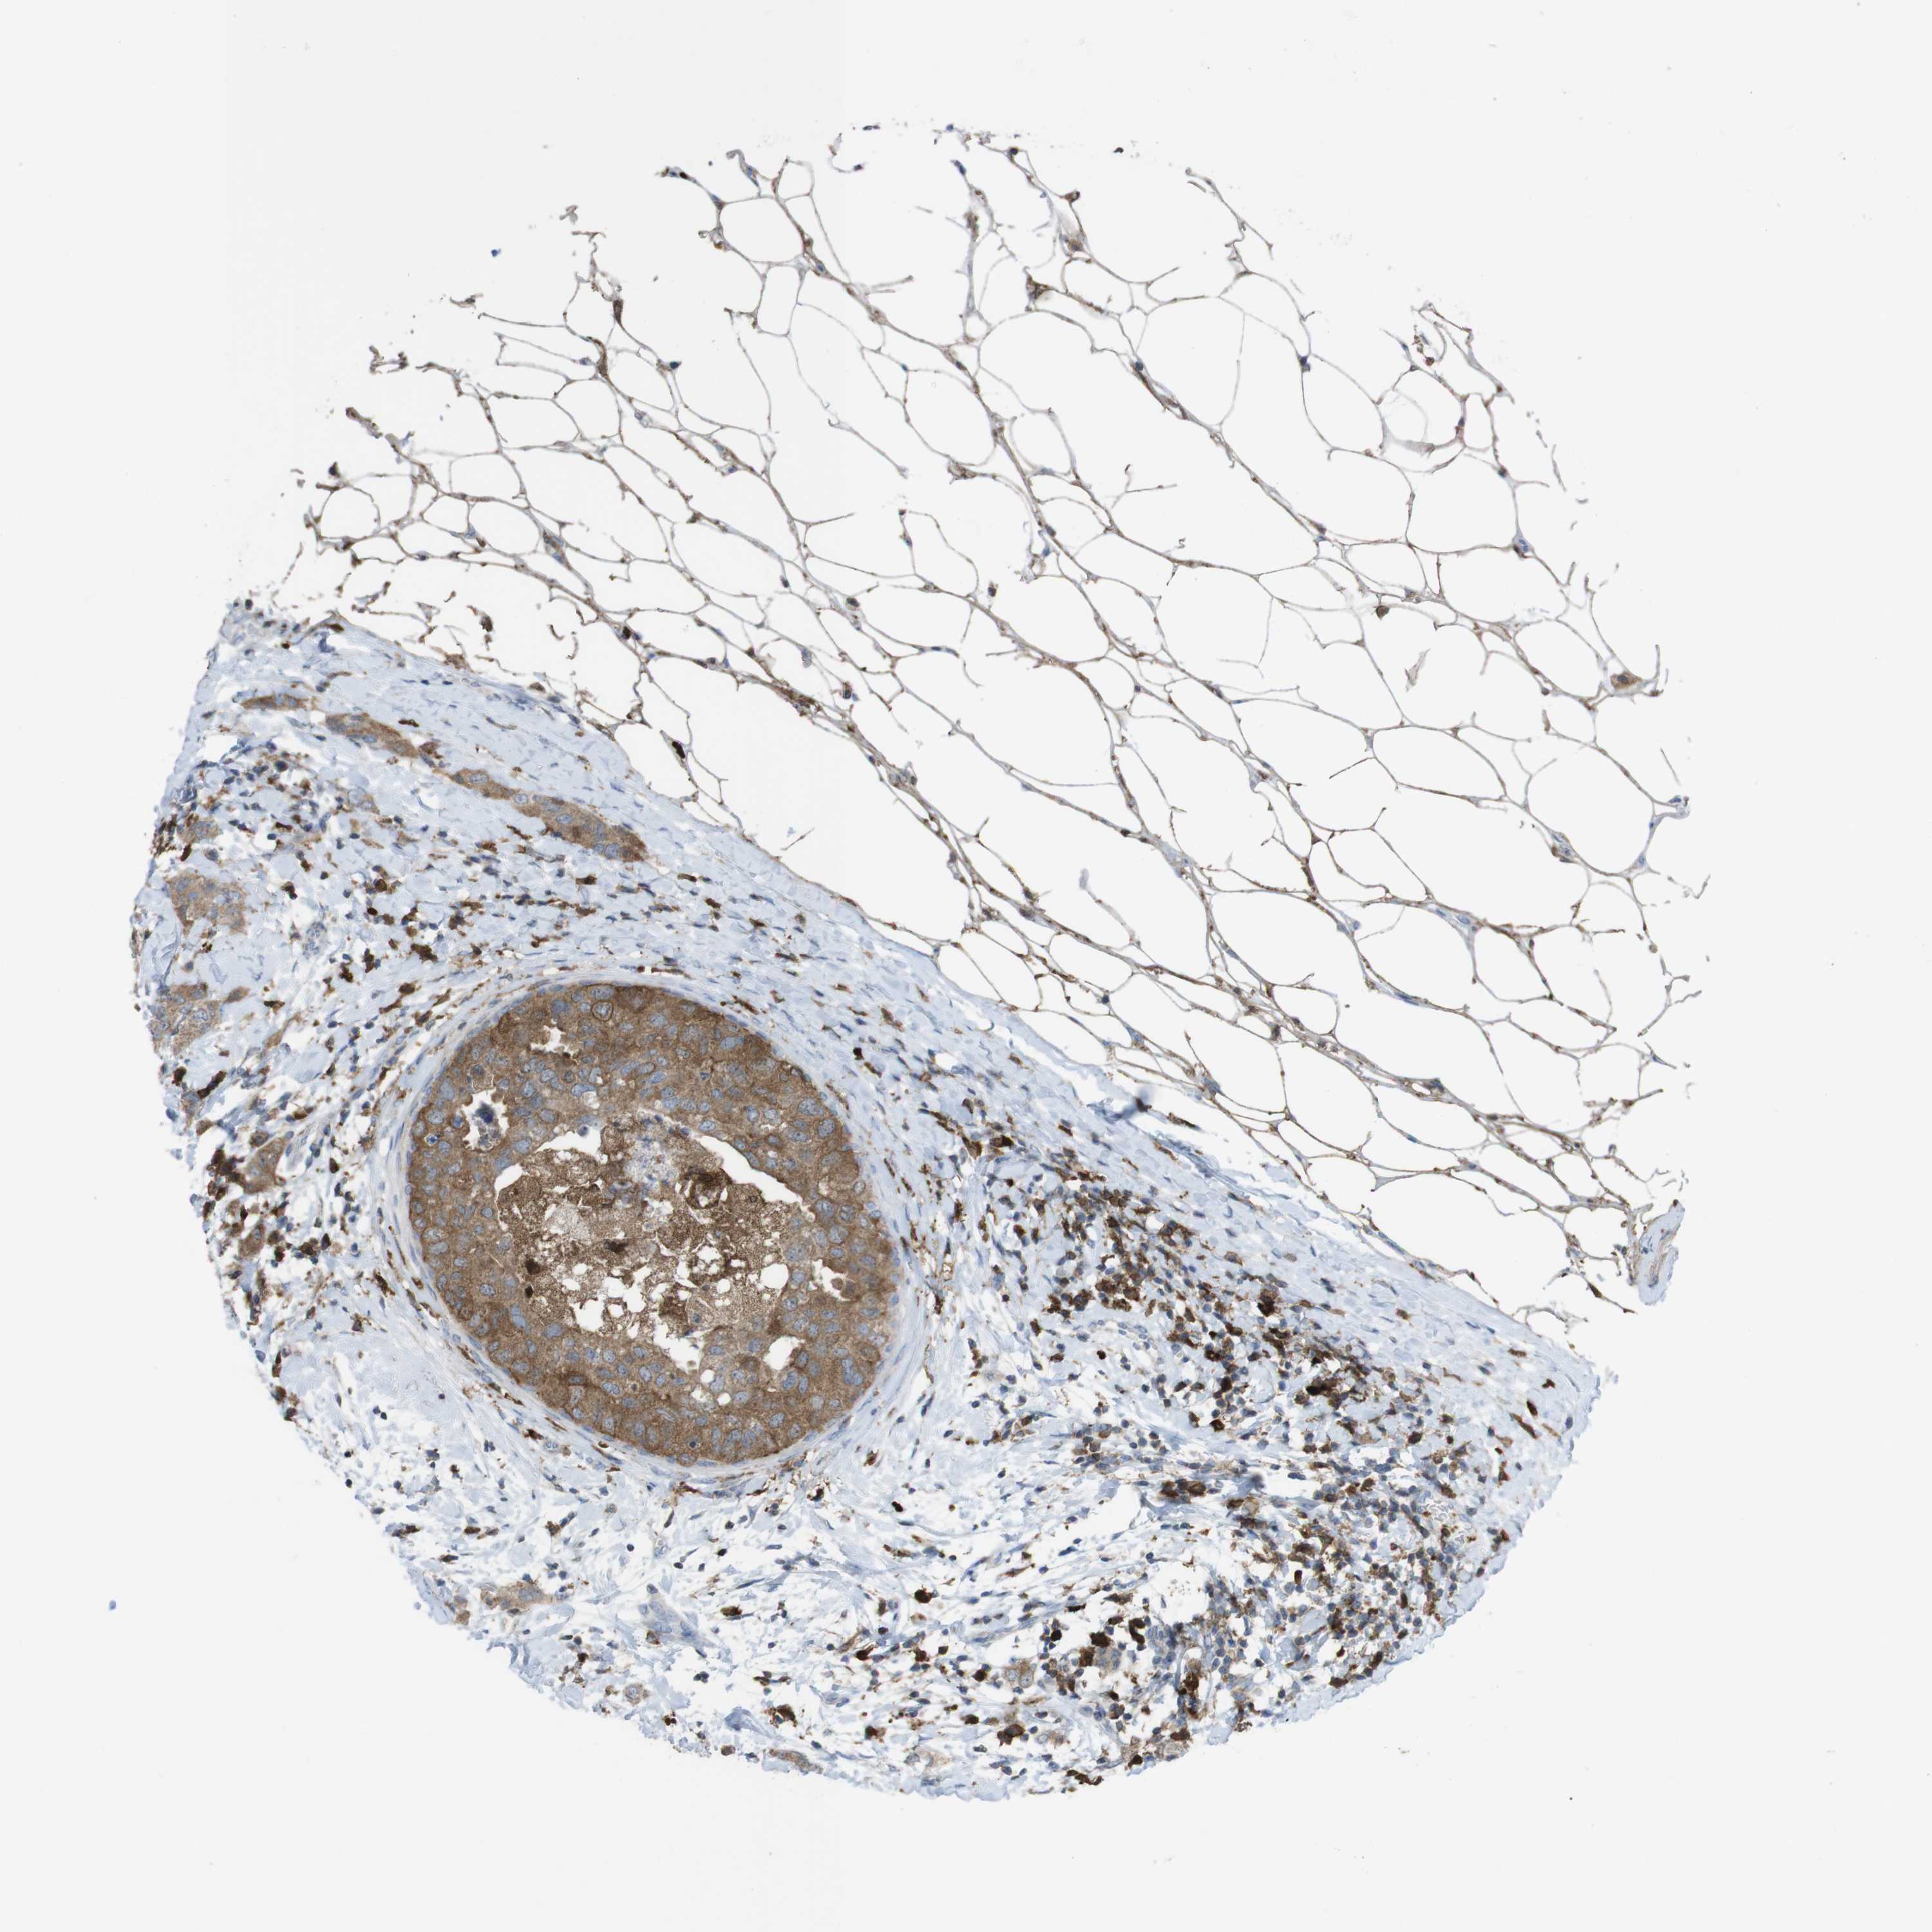

CANCER BREAST CANCER Show tissue menu

BRCA TCGA BRCA VALIDATION PROTEIN EXPRESSION